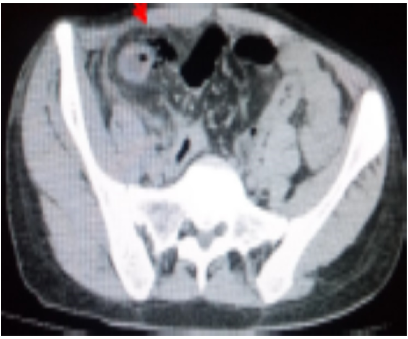

A body computed tomography was performed, revealing circumferential parietal thickening of the last ileal loop, measuring 10 mm and extending over 30 cm, with arterial enhancement and parietal loss of substance of an ileal loop estimated at 02 cm in extent, located 10 cm from the ileo-caecal junction, with multiple air bubbles and fluid opposite. This was associated with infiltration of mesenteric fat. The imager concluded that the peritonitis was due to perforation of the last ileal loop in Crohn's disease (figures 1 and 2).

Figure 1.Computed tomography section showing extra-digestive air bubbles opposite the last ileal loop (red arrow)